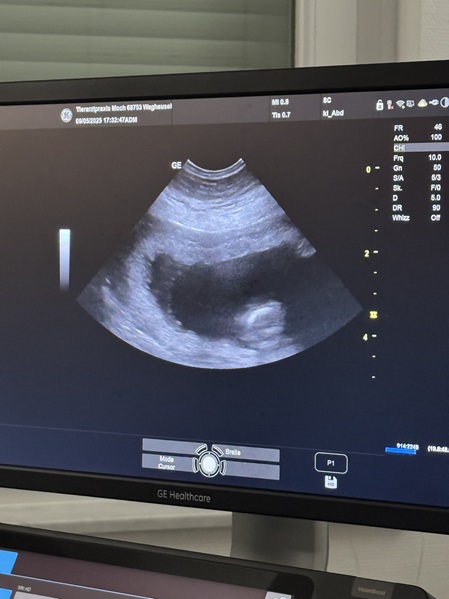

Am 05.Juni 2025 erblicken unsere E-chens das Licht der Welt

4 Mädchen und 5 Jungs + ein Sternenmädchen

Unsere E - chens kamen per Kaiserschnitt zur Welt.